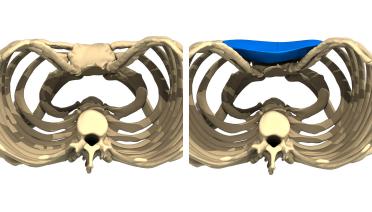

La tecnica di impianto su misura è una tecnica chirurgica minore che consiste nel riempire la concavità creata dal Pectus con un impianto personalizzato. Si tratta di un intervento rapido, a basso rischio, con un risultato immediato e una breve convalescenza.

In questa pagina, troverà i risultati di questa operazione a seconda del tipo di Pectus : mediale, asimmetrico, più o meno profondo o lungo.